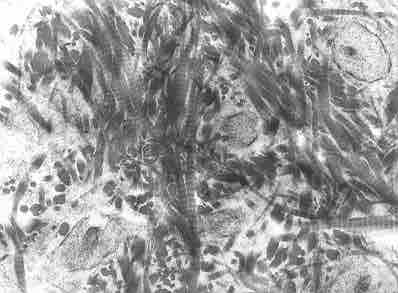

Woven bone

Woven bone is characterized by the irregular organization of collagen fibers and is mechanically weak.

Woven bone is found on the growing ends of an immature skeleton or, in adults, at the site of a healing fracture. Woven bone is characterized by the irregular organization of collagen fibers and is mechanically weak, but forms quickly.

The criss-cross appearance of the fibrous matrix is why it is referred to as woven. It has a high proportion of osteocytes to hard inorganic salts that leads to its mechanical weakness.